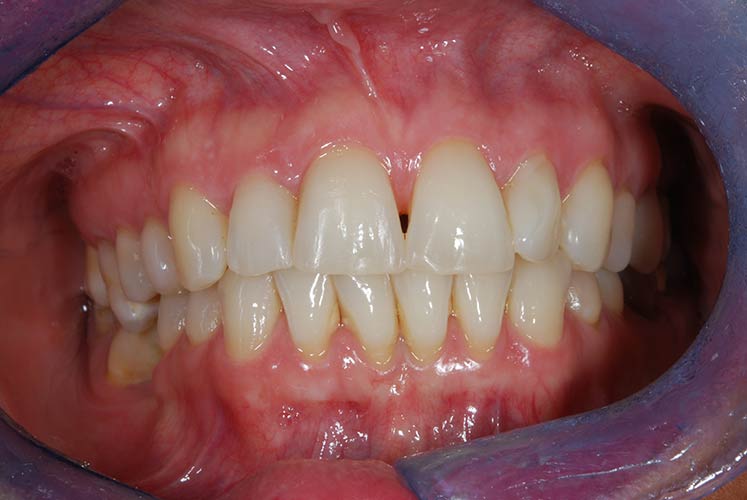

Con protesi fissa superiore e protesi fissa inferiore

I denti irrecuperabili dell'arcata superiore ed inferiore del paziente di anni 65

sono stati sostituiti da 10 impianti, cioè protesi radicolari endo-ossee che sostengono le protesi fisse superiore ed inferiore.